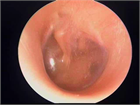

診断

1. 鼻すすり型耳管開放症と非鼻すすり型耳管開放症を区別して診断する。